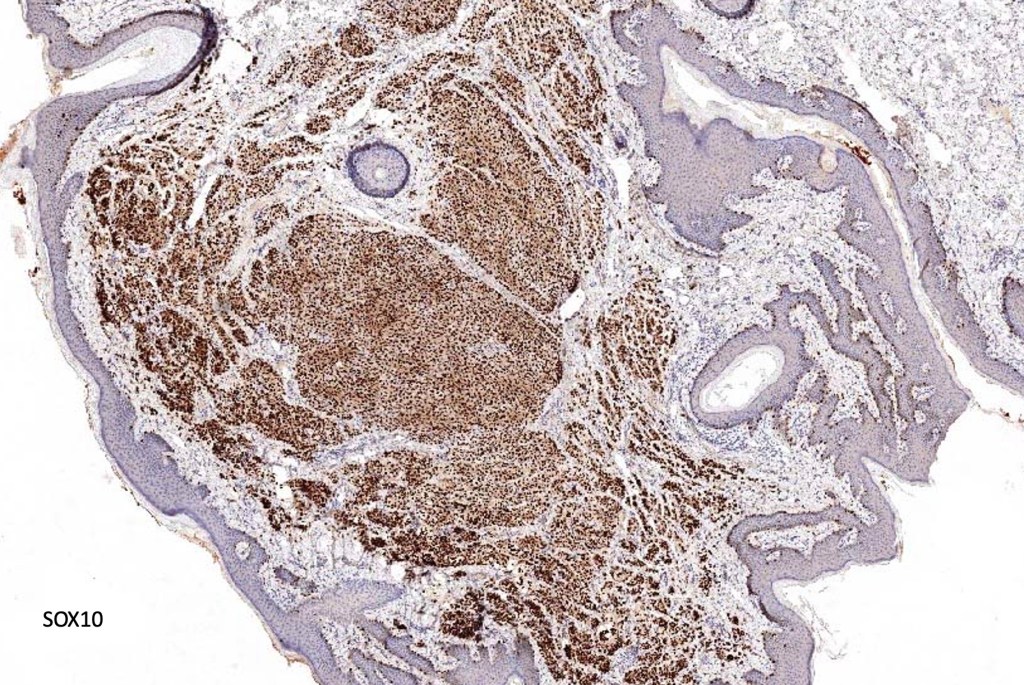

. In some balloon cell nevi, the microvesicles may result in nuclear scalloping reminiscent of a sebaceous tumor. In cases where there is real doubt, immunohistochemistry (S100), SOX10) will resolve the problem.